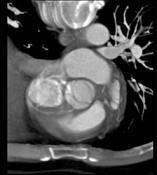

下面一组图像考虑为 ( )A、正常的主动脉瓣B、变异的主动脉瓣(两个瓣膜)C、正常的二尖瓣D、正常的三尖瓣E、正常的肺动脉瓣

问题 下面一组图像考虑为 ( )

选项 A、正常的主动脉瓣 B、变异的主动脉瓣(两个瓣膜) C、正常的二尖瓣 D、正常的三尖瓣 E、正常的肺动脉瓣

答案 B